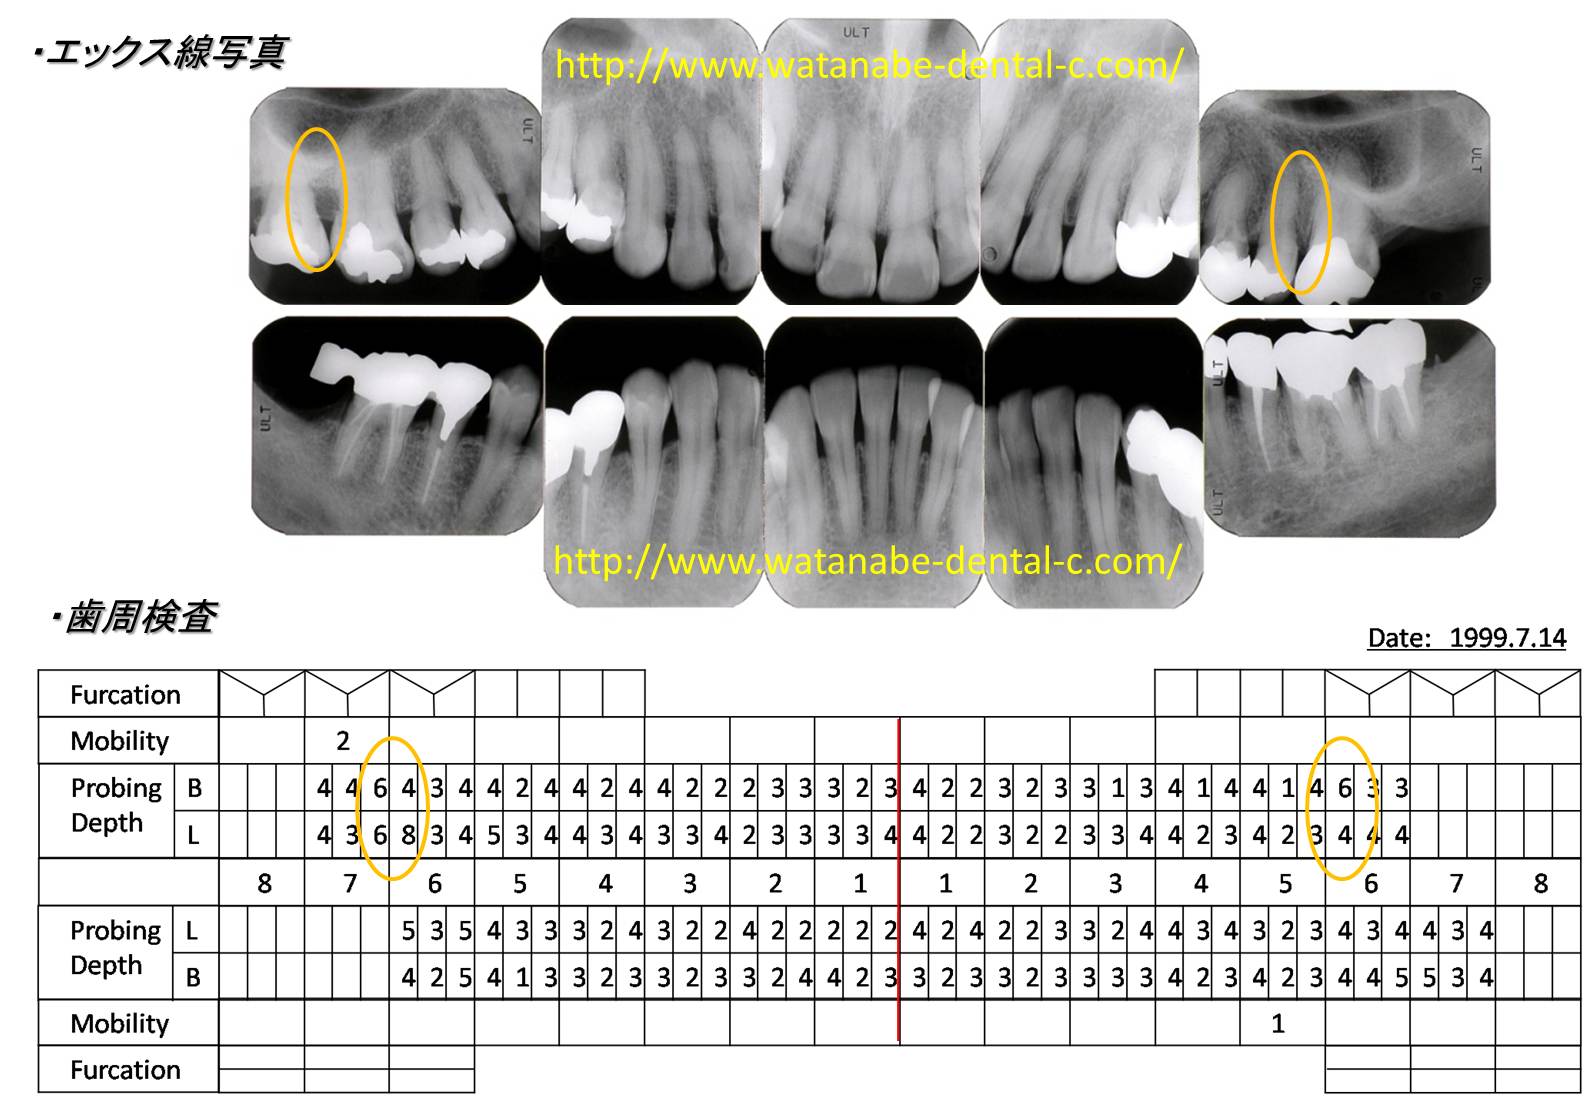

インレー(小さな金属)が外れて来院されました。特に上顎舌側歯肉の炎症が見られます。エックス線所見および歯周組織検査です。オレンジの○部分の骨吸収像と同部位に6mm以上の歯周ポケットが認められます。